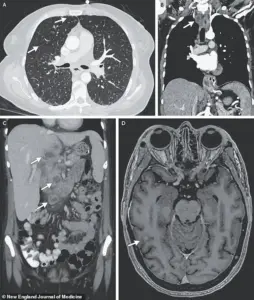

A harrowing case study illustrates the devastating consequences of undiagnosed and untreated TB.

A woman’s medical scans revealed nodules in multiple organs, including her lungs, liver, pancreas, and brain.

Her journey through the healthcare system was fraught with complications, including a 33-day hospitalization for antibiotics, steroids, and antiretroviral therapy to combat HIV.

Despite initial recovery, she was readmitted months later for depression and suicidal ideation, linked to housing instability.